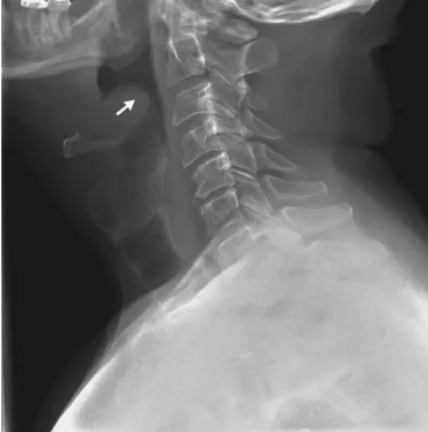

진단 (Diagnosis)

측면 경부 X-ray: 부어오른 후두개를 나타내는 '엄지손가락 징후'(thumb sign) 확인

확진: 수술방과 같이 기도 확보가 준비된 환경에서 직접 후두경 검사로 부어오른 후두개를 확인